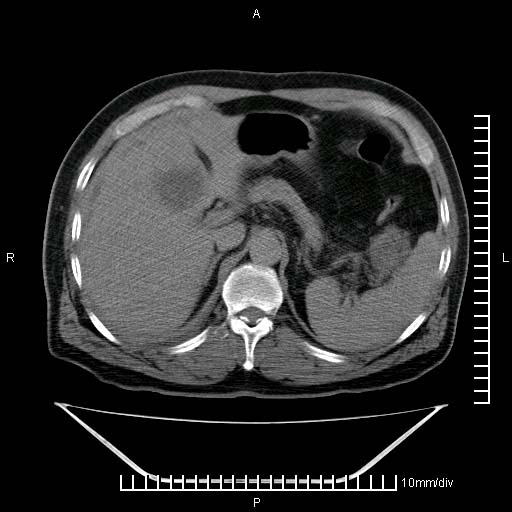

标题: CT25082:肝脏增强:男性,70岁 [打印本页]

标题: CT25082:肝脏增强:男性,70岁

患者以心脏疾病收住院,腹部无明显症状,b超查肝脏有占位。

增强效果不理想。考虑转移,胆囊壁明显增厚,不排除胆囊癌肝转移。

病灶无强化,考虑囊肿。

牛眼征,中心坏死无强化,外缘强化,最外缘又见低密度,考虑转移,与脓肿鉴别

肝内多发转移瘤,右下肺炎症并少量胸水。胃壁增厚建议胃镜,胰尾部“病变”为肠管。

1)肝脏多发性转移瘤(不排除胰尾癌转移所致可能)。2)腹水。3)右侧少量胸腔积液。

ct25082 结果:转移瘤

外院mr结果:胰尾恶性占位。